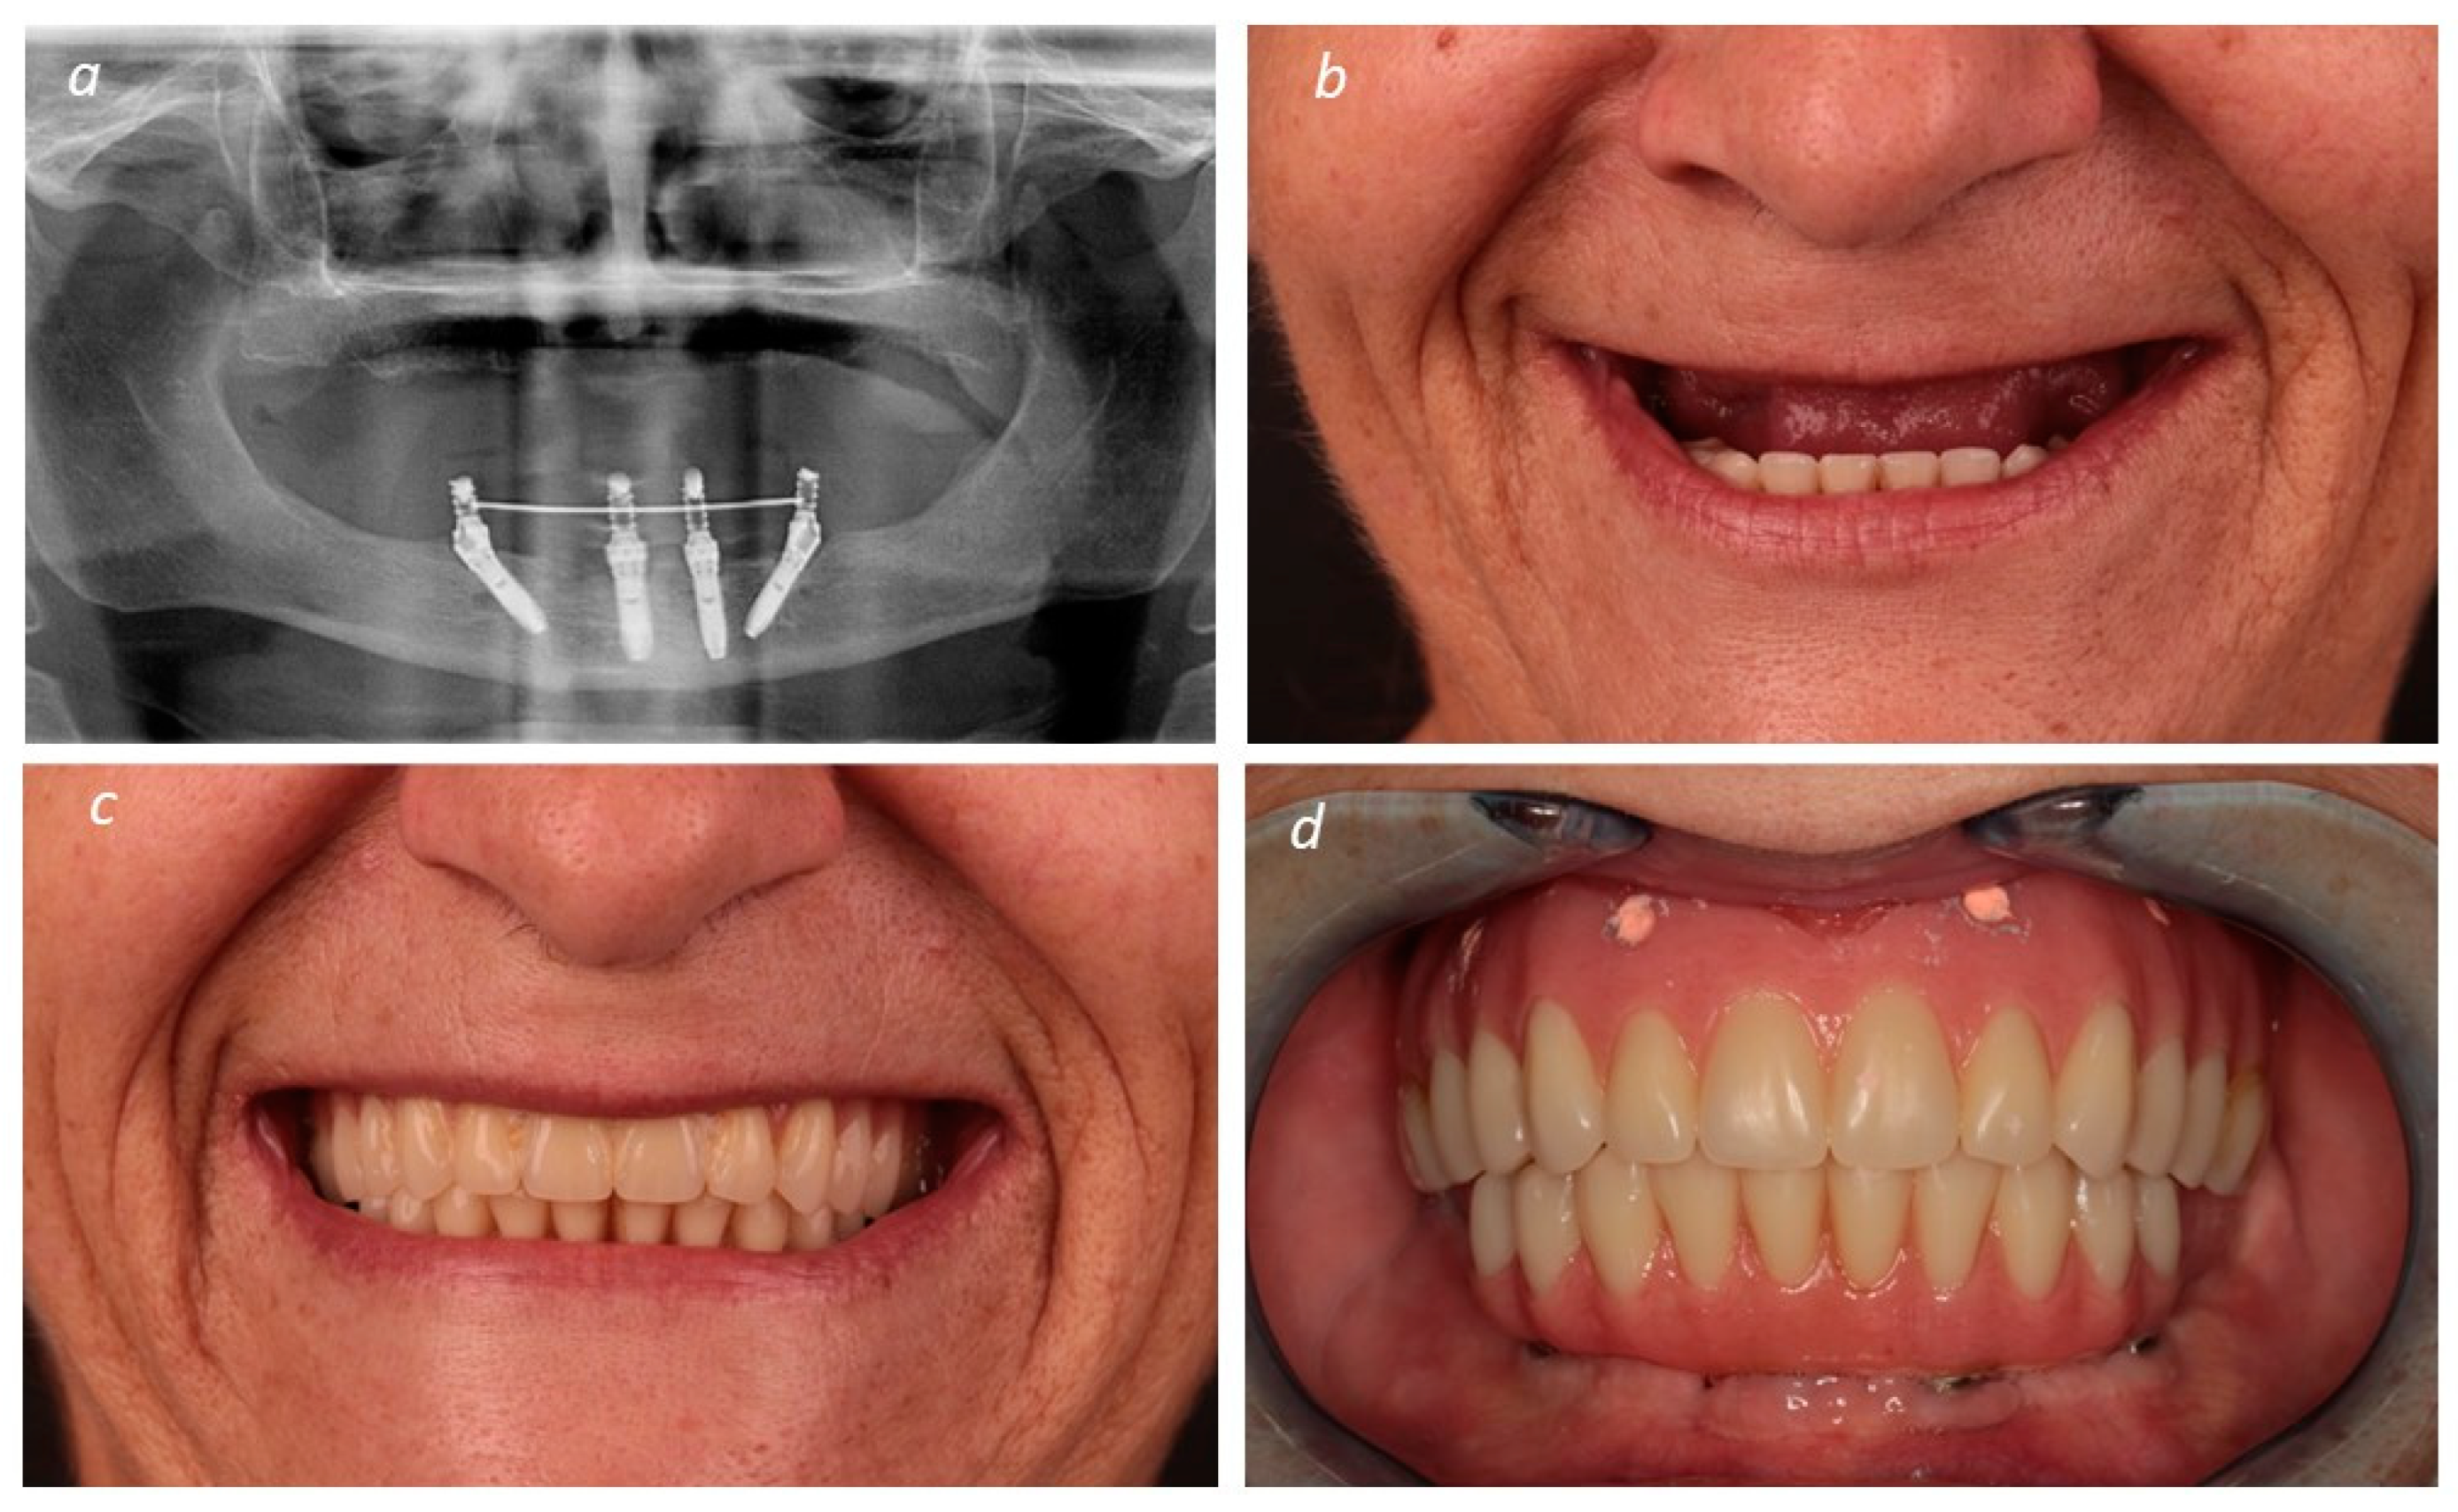

A New Full Digital Workflow for Fixed Prosthetic Rehabilitation of Full-Arch Edentulism Using the All-on-4 Concept

2. Materials and Methods

Description of the Technique

3. Results